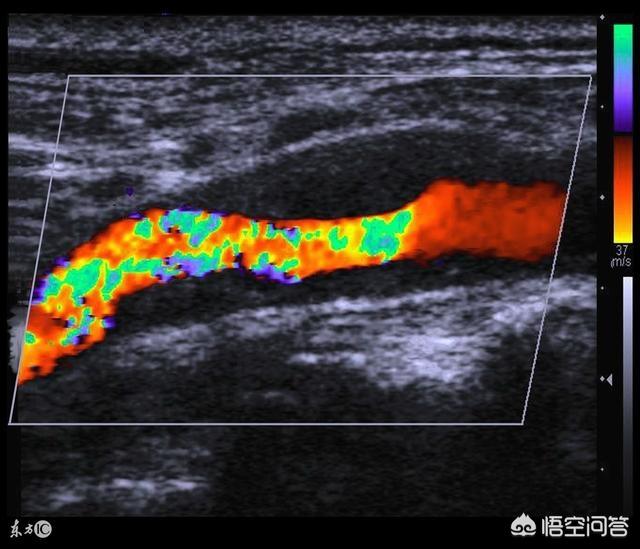

La plaque carotidienne peut être détectée par échographie. Il s'agit de la capacité de l'organisme à comprendre les vaisseaux artériels de plus grande taille par le biais d'un test non invasif. Dans des circonstances normales, l'épaisseur de la membrane interne et de la couche intermédiaire (IMT) ne dépasse pas 0,9 mm ; si l'IMT est >0,9 mm, on parle d'épaississement intima-média de l'artère carotide ; si l'IMT est >1,3 mm, on parle de plaque de l'artère carotide.

La plaque carotidienne est principalement détectée par échographie. Dans des circonstances normales, l'épaisseur de la membrane interne et de la couche intermédiaire (IMT) ne dépasse pas 0,9 mm ; si l'IMT est >0,9 mm, on parle d'épaississement de l'intima-média carotidien ; et si l'IMT est >1,3 mm, on parle de plaque de l'artère carotide. L'importance de la découverte d'une plaque carotidienne est la suivante : elle montre que les vaisseaux sanguins ont commencé à se durcir, mais il s'agit également d'une manifestation du vieillissement naturel de l'organisme. Un tiers des adultes chinois présentent des plaques d'athérosclérose carotidiennes, tout comme la peau se relâche lorsque l'on vieillit, cela indique simplement que les vaisseaux sanguins sont vieux, et il n'y a pas lieu de s'inquiéter outre mesure. Deuxièmement, une partie des plaques carotidiennes à haut risque (20 à 30 %) fera un accident vasculaire cérébral, et les plaques carotidiennes dans cette partie de la population doivent être traitées activement. Enfin, une minorité de plaques carotidiennes provoquant une sténose de l'artère carotide peut également nécessiter une intervention chirurgicale.

Les plaques carotidiennes les plus courantes chez le grand public sont celles qui ne provoquent pas de sténose sévère, comme les plaques dont la sténose est généralement inférieure à 50 %. Alors, ces patients ont-ils besoin d'un traitement médicamenteux ou non ? D'une manière générale, l'échographie carotidienne permet de classer les plaques carotidiennes en plaques hypoéchogènes, plaques isoéchogènes, plaques hypoéchogènes et plaques échogènes hétérogènes, qui ne sont pas couramment observées, grâce à l'image en échelle de gris.

D'une manière générale, les plaques hypoéchogènes, également appelées "plaques molles", sont relativement riches en lipides, relativement instables et nécessitent généralement la prise de statines par voie orale. Les plaques hypoéchogènes, également appelées "plaques dures", sont relativement stables et la décision de prendre une statine dépend du nombre de facteurs de risque et de l'importance des autres affections. Il n'est pas prudent de traiter une plaque dure avec une statine. Les plaques isoéchogènes, parfois appelées "plaques à écho mixte", peuvent être considérées comme des "plaques mixtes", c'est-à-dire des plaques à la fois dures et molles, auquel cas les statines orales peuvent être envisagées en conjonction avec la stratification du risque du patient. Examinez de plus près les trois images ci-dessous.